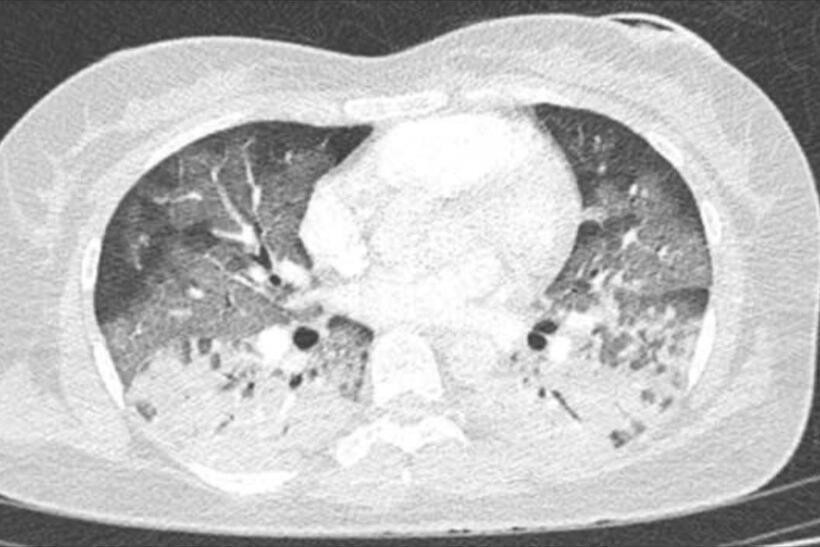

Khi chuyển đến Bệnh viện Nhân dân Gia Định phổi cô gái bị tổn thương đông đặc. Ảnh: Dân Trí.

Tạp chí Tri Thức dẫn lời ThS.BS Võ Văn Trắng, Đơn vị Hồi sức tích cực tim mạch, Bệnh viện Nhân dân Gia Định (TP.HCM), cho biết thời điểm được chuyển đến khoa Cấp cứu, bệnh nhân được chẩn đoán tổn thương đa cơ quan liên quan sốc phản vệ, đặc biệt nghiêm trọng là tổn thương cơ tim cấp và hội chứng suy hô hấp cấp (ARDS).